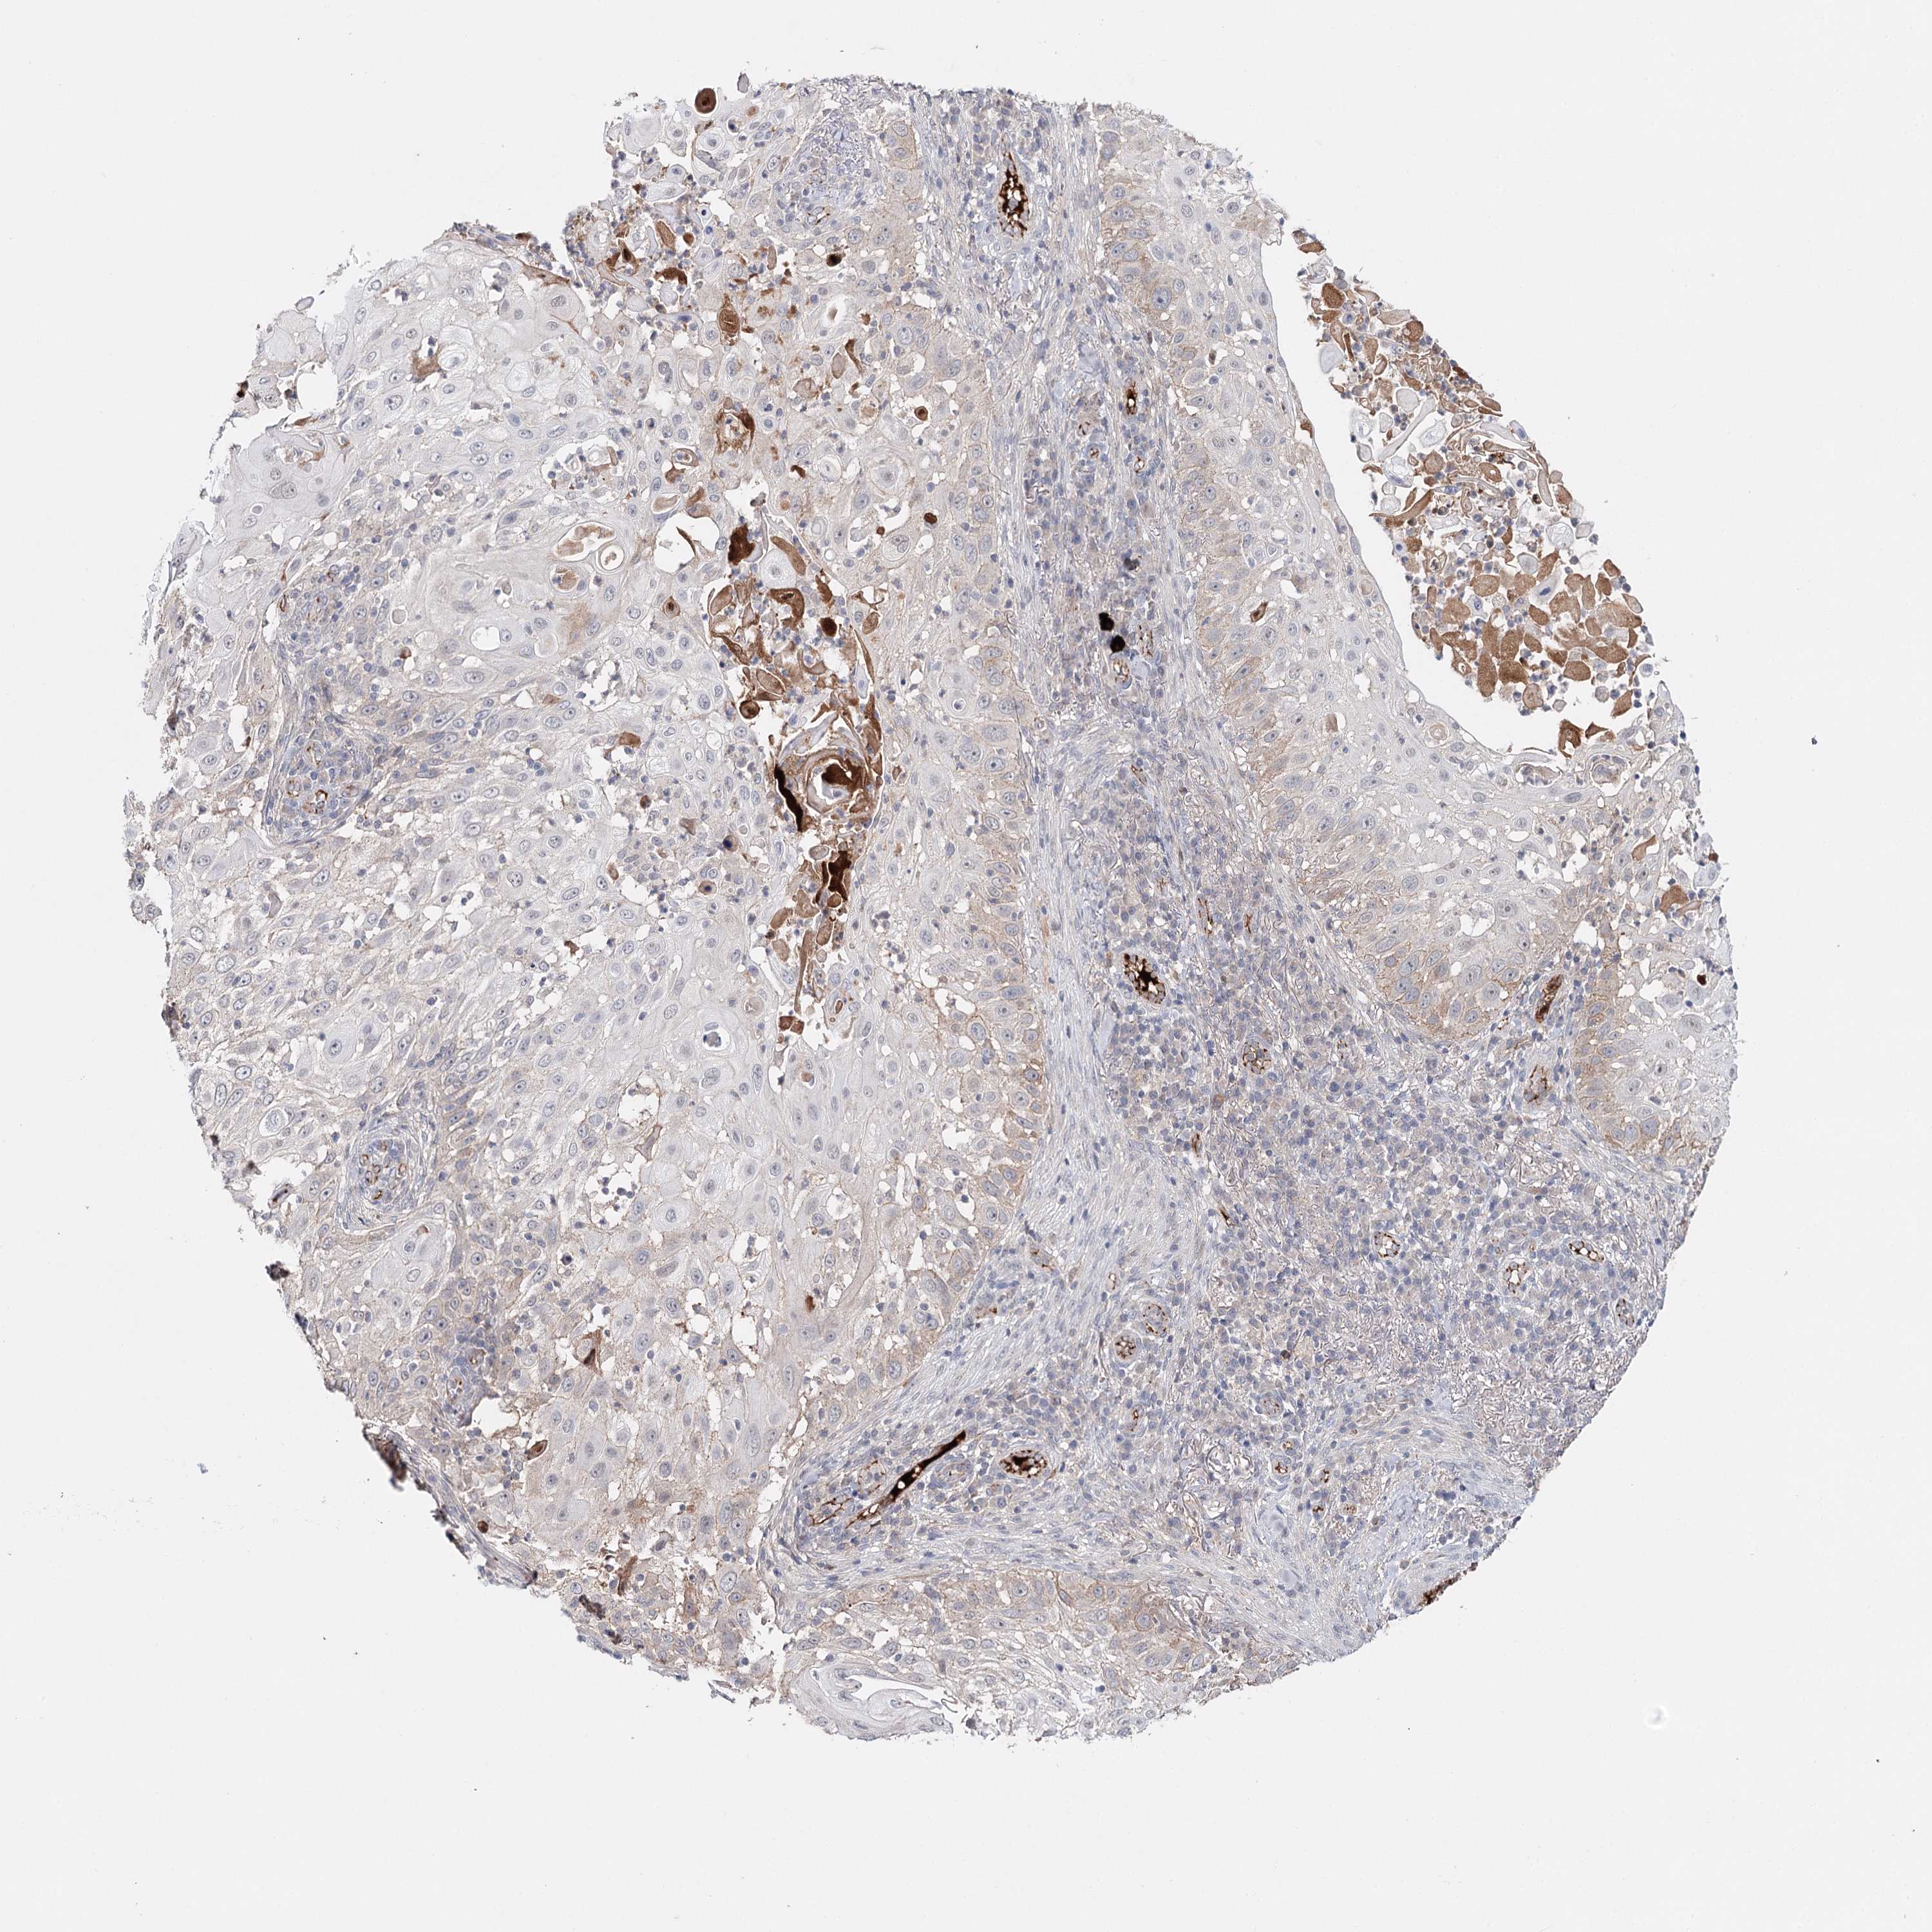

SKIN CANCER - Protein expressioni

A mouse-over function shows sample information and annotation data. Click on an image to view it in a full screen mode. Samples can be filtered based on level of antibody staining by selecting one or several of the following categories: high, medium, low and not detected. The assay and annotation is described here.

Antibody stainingi

Antibody staining in the annotated cell types in the current human tissue is reported as not detected, low, medium, or high, based on conventional immunohistochemistry profiling in selected tissues. This score is based on the combination of the staining intensity and fraction of stained cells.

Each image is clickable and will lead to virtual microscopy that enables deeper exploration of all samples and also displays staining intensity scores, fraction scores and subcellular localization as well as patient and tissue information for each sample.

Antibody CAB037334

Staining

High

Medium

Low

Not detected

Intensity

Strong

Moderate

Weak

Negative

Quantity

>75%

75%-25%

<25%

None

Location

Nuclear

Cytoplasmic/membranous

Cytoplasmic/membranous,nuclear

Squamous cell carcinoma, NOS

Squamous cell carcinoma, metastatic, NOS